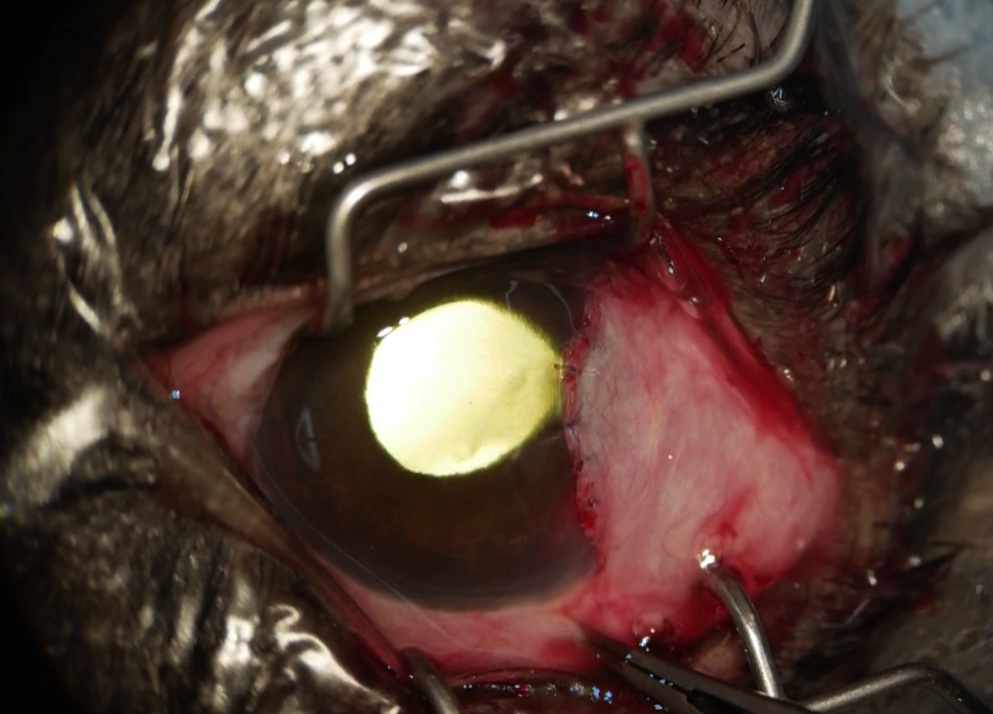

今症例に対しては、穿孔した部位の保護、治癒促進のため、結膜フラップ術を実施しました。

穿孔部位の近くの結膜を切開し、移動して縫合しました。

今回は経過観察の途中で、フラップ部位が脱落してしまいましたが、

その時にはすでに角膜損傷は治癒されていました。